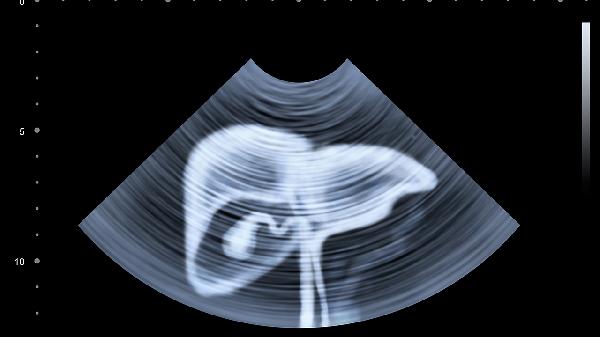

对于肿瘤负荷较大的肝癌晚期患者,单独使用中医治疗难以控制肿瘤进展,可能出现进行性肝功能恶化、门静脉高压、癌性腹水等严重并发症。肿瘤自发性破裂出血、肝性脑病等危急情况必须立即采用西医介入治疗。部分中药成分可能干扰现代医学检验结果,影响疗效评估。民间流传的抗癌偏方缺乏科学验证,可能加重肝脏代谢负担。

肝癌晚期患者建议在肿瘤专科医生指导下制定中西医结合治疗方案。定期进行影像学检查和肿瘤标志物监测,根据病情变化及时调整治疗策略。保持适度蛋白质摄入,控制钠盐预防腹水加重,适当运动维持肌肉含量。出现意识改变、呕血、剧烈腹痛等急症表现须立即就医。心理支持对改善生活质量同样重要,可配合情志调理等中医心理疗法。